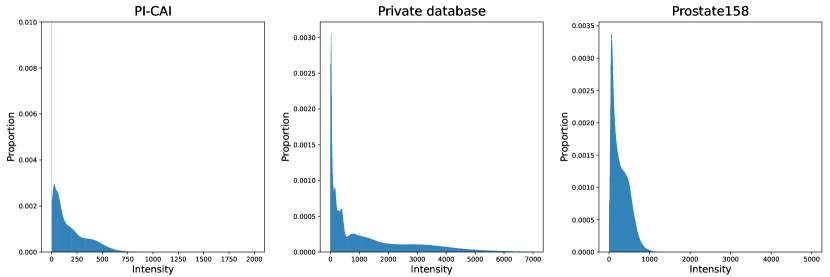

Both T2-weigthed (T2w) and apparent diffusion coefficient (ADC) MR maps were used as input channels. The latter modality was registered to the former, all images were resampled to a mm3 pixel size and cropped to volumes. Images intensities were linearly normalized into the range [0, 1] for each patient and each modality. More details about these datasets can be found on Appendices A and B, including lesion volume distributions and histograms of intensities for T2-weighted imaging and ADC maps.

Appendix B Characteristics of MRI modalities for each database